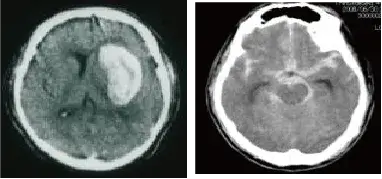

脳出血(左)くも膜下出血(右) -

脳出血・くも膜下出血

急性期に専門医が適切な管理と治療を行うことで、血腫の増大を防ぎ、再出血を防止できます。脳血管撮影、CT angiography、MRI等先進の医療機器を24時間稼働させ、原因に応じた治療を行います。